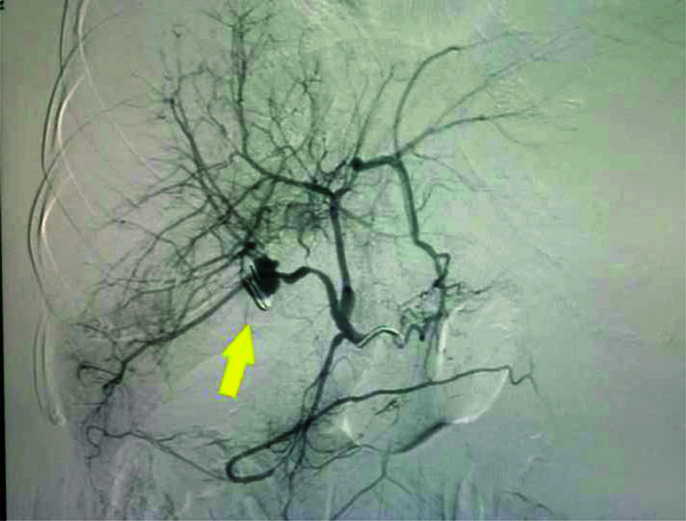

图 2.

胶水和碘油栓塞后血管造影显示假性动脉瘤不透明,充满(黄色箭头)并保留肝动脉(红色箭头)。